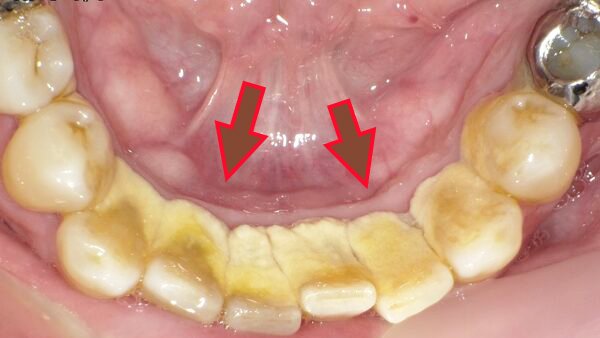

歯石とは、歯の表面に付着したプラーク(歯垢)が唾液中のカルシウムやリン酸と結びつき、硬く石灰化したものです。普段の歯みがきでは除去できず、数日~数週間で固い歯石に変化します。

一度歯石になると歯ブラシでは取れず、歯周病や口臭、虫歯の原因となります。そのため歯石取りは歯科医院で定期的に受けるべき重要な処置です。

見える部分の歯石を取っても、隠れた歯石が残っていることが多いため、プロによる歯石取りが欠かせません。